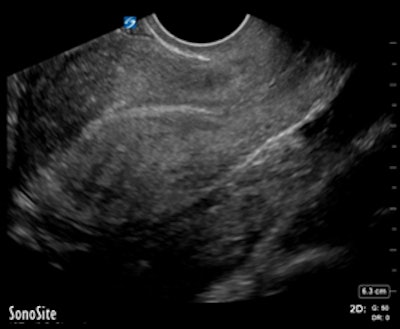

While point-of-care ultrasound is becoming more common in managing first-trimester patients in the emergency setting, interpretation of these exams is often complicated and difficult, Wallace-Severa said. Ultrasound is an operator-dependent modality, and misinterpretation can have fatal consequences.

At Santa Barbara Cottage Hospital, ER physicians perform and interpret bedside obstetric ultrasounds -- frequently just transabdominal studies -- using compact ultrasound systems, while radiology ultrasound exams, which include both transabdominal and transvaginal studies, are supervised and interpreted by radiologists. The radiology ultrasound exams are performed in the radiology department by sonographers certified by the American Registry for Diagnostic Medical Sonography (ARDMS), who are available 24/7 to scan patients, according to the group.